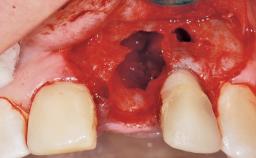

This 43-year-old male patient, a non-smoker, came to our practice because of a fracture of tooth 12 caused by a bicycle accident. Due to the combined para- and infrabony crown and root fracture, tooth extraction, and subsequent implant placement were suggested to the patient as the therapy of choice. The patient had high esthetic expectations with regard to the treatment outcome and asked for an immediate fixed provisional restoration. His individual esthetic risk profile summed up to a medium esthetic risk.

Placement Protocol Immediate implant placement

Socket Integrity Sufficient, with intact bone walls

Bone Volume Sufficient, with intact walls

Risk of Complications High